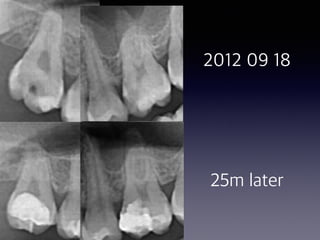

#2, #14 direct pulp capping

follow-up

(30 male)

2012 09 18

25m later

8m later